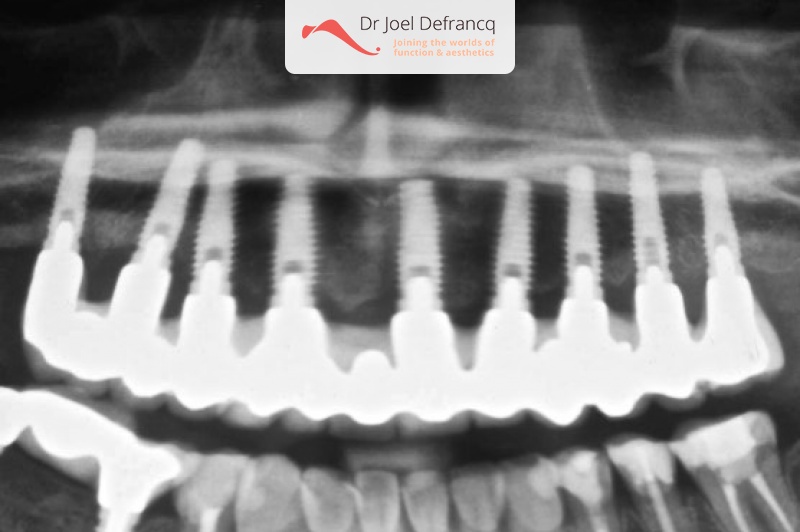

Behandeling tandheelkundige implantaten

- Vaste tanden op implantaten (bovenkaak)

- Implantaten met osteotomie

- Implantaten met beenopbouw